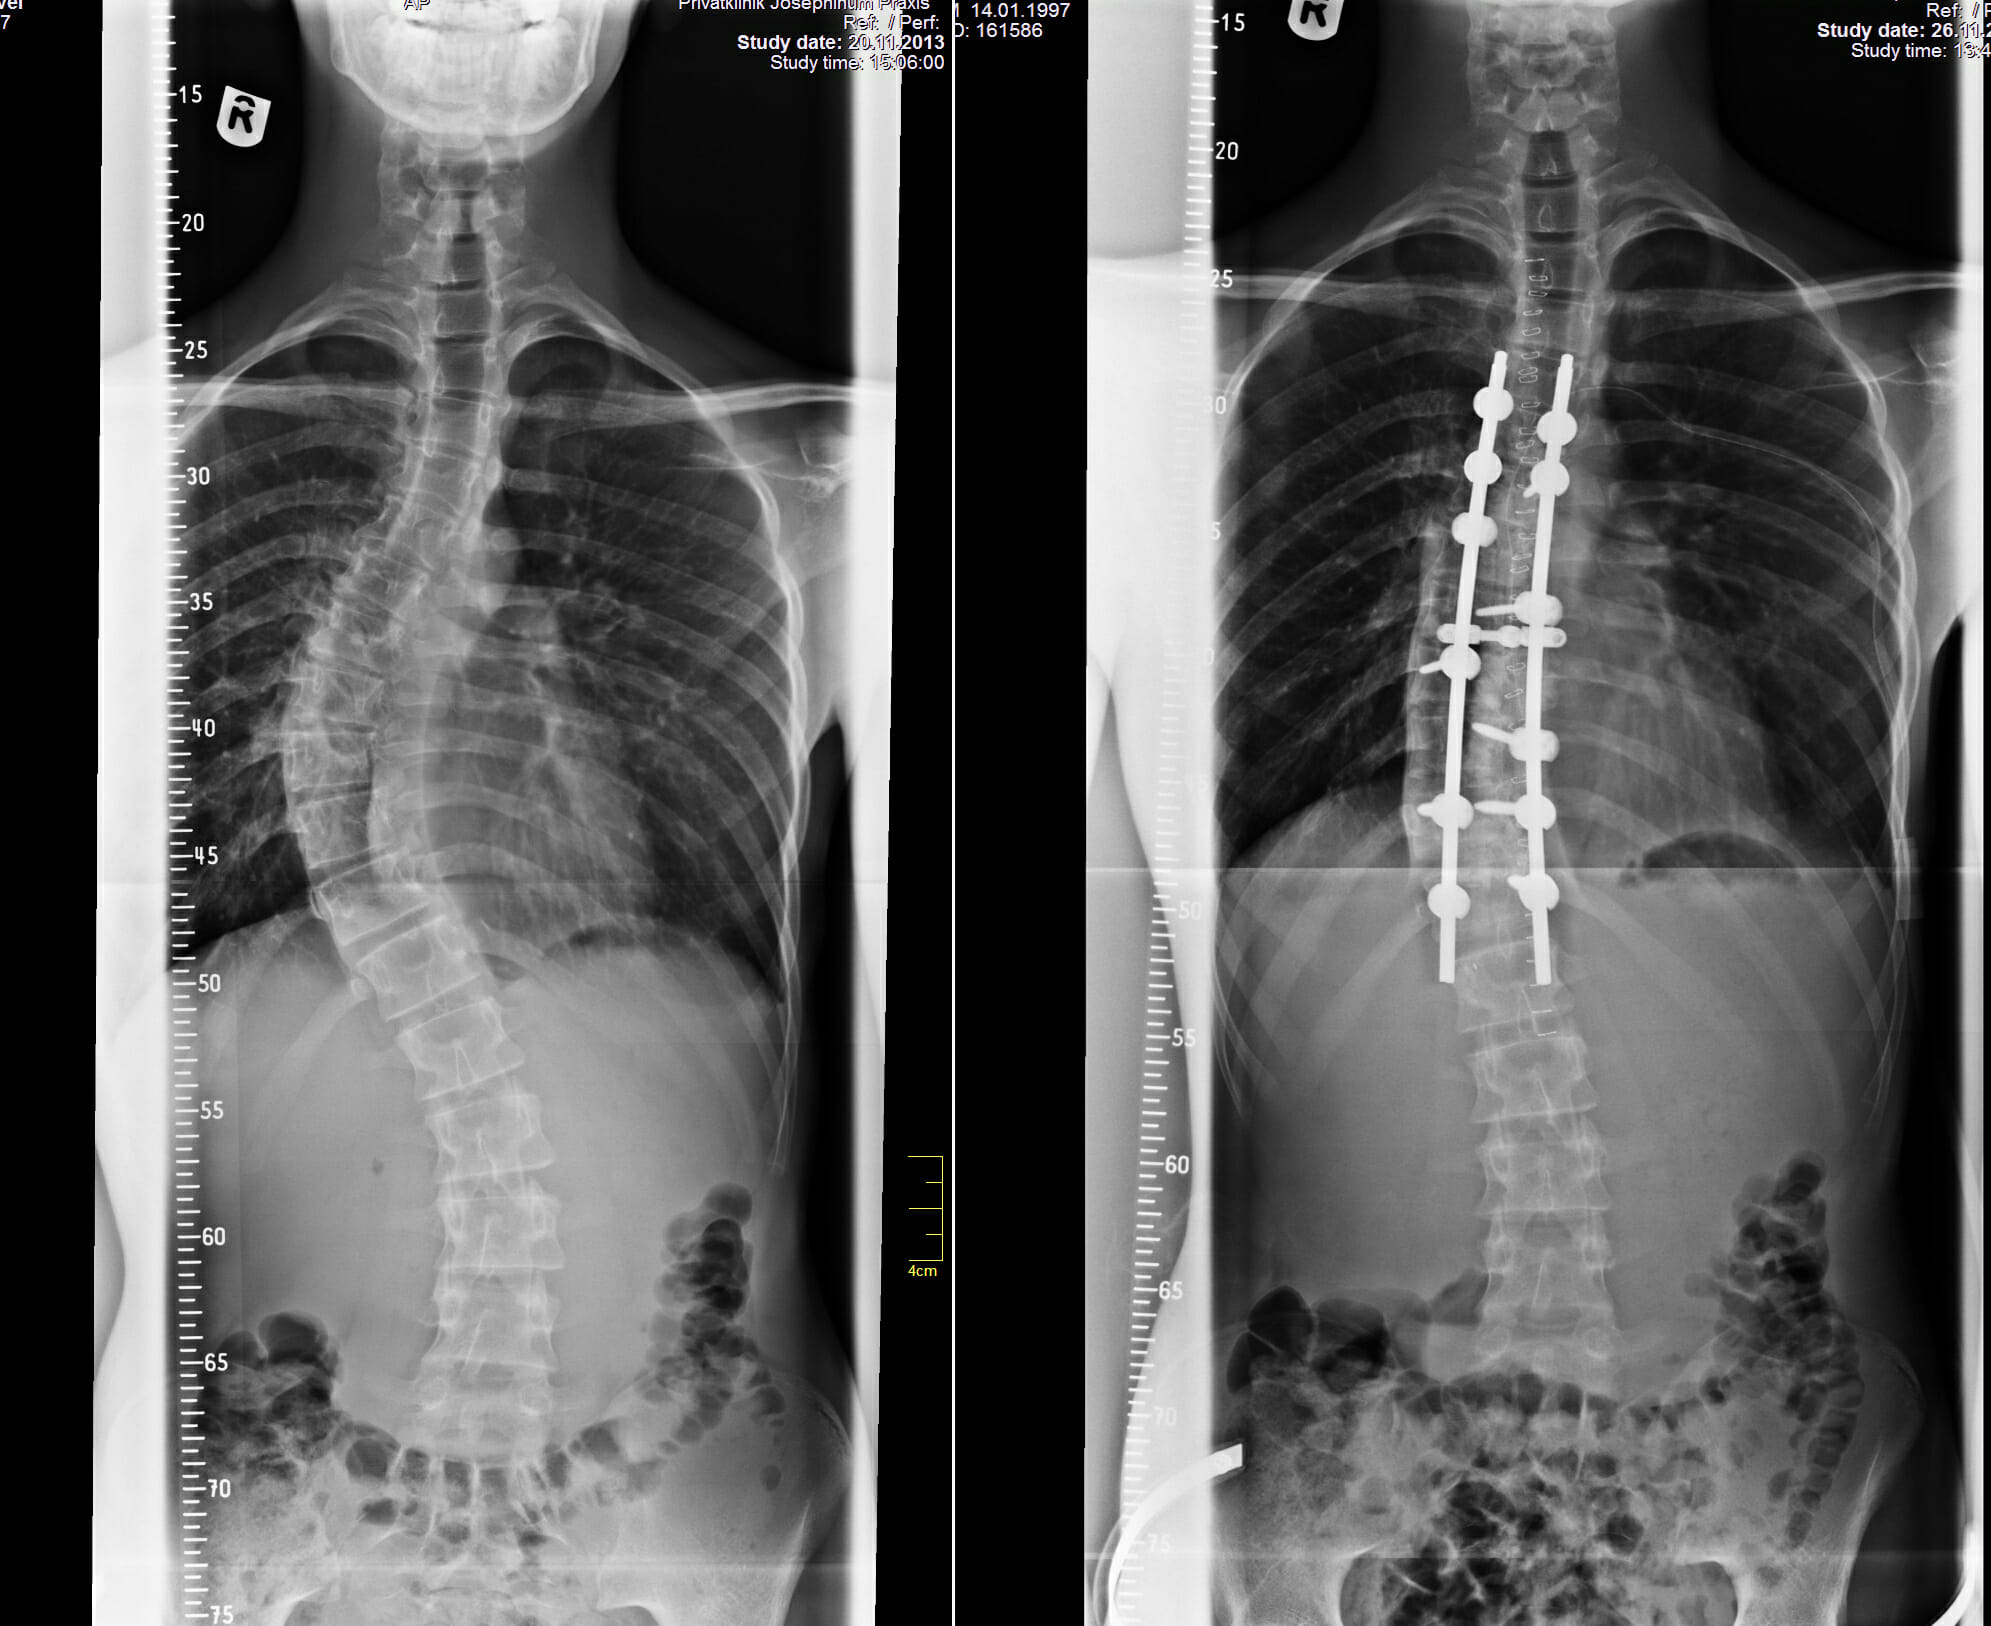

Am 22. November war’s so weit: Dr. Linhardt und sein Team führten im Münchener Klinikum ‚Josephinum‘ in stundenlanger Arbeit die in vielerlei Hinsicht komplizierte Operation an unserem 16-jährigen Pasha aus; davon abgesehen, dass die Wirbelsäule sagittal, horizontal und vertikal begradigt werden musste – und das über 8 Wirbelkörper – hatte sich alleine in den fünf Monaten die rechtsgerichtete Krümmung von 40,4° auf mehr als 48° verschlimmert.

Der Erfolg ist wirklich sensationell und was für eine unglaubliche Freude, Pasha

8 Tage nach seiner Operation mit strahlenden Augen und seit vielen Jahren erstmals geradem Rücken durch die Klinik laufen zu sehen.

In Kaliningrad wie auch im deutschen Team herrscht große Freude und Erleichterung; nun ist dem Fortschreiten der Skoliose ein Ende gesetzt und Pasha kann aufrechten Gangs freudvoll sein weiteres Leben gestalten.

- Nach erfolgter OP (rechts)

- Ein erfreuliches Ergebnis